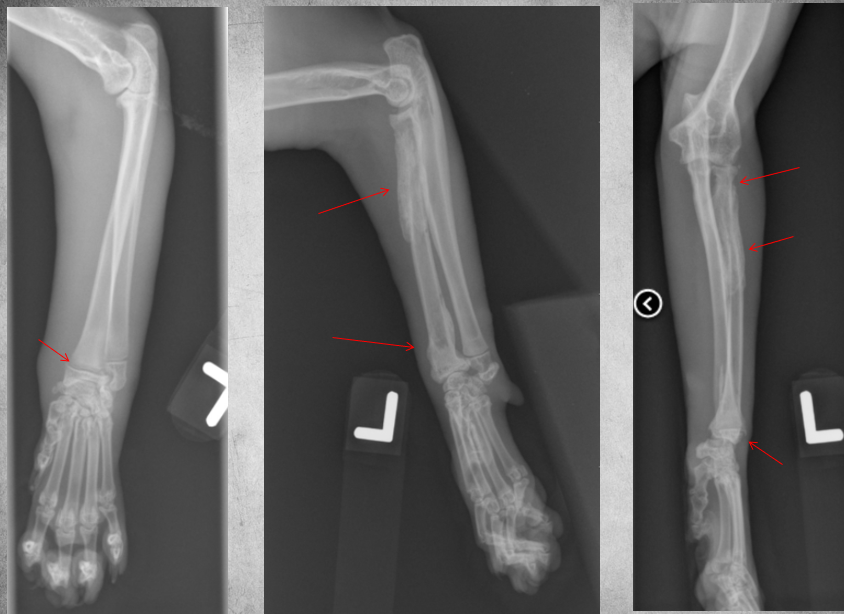

4 years old male castrated Labrador cross

Sudden and acute lamness while playing with ball

Osteolysis of the proximal third of the tibial diaphysis and very mild irregular periosteal reaction.

There is a short oblique fracture through the tibial diaphysis with several small associated fragments, mild medial and proximal displacement of the distal segment. A transverse fracture of the fibula is present at the same level.

Diagnosis: Osteosarcoma with pathologic fracture.